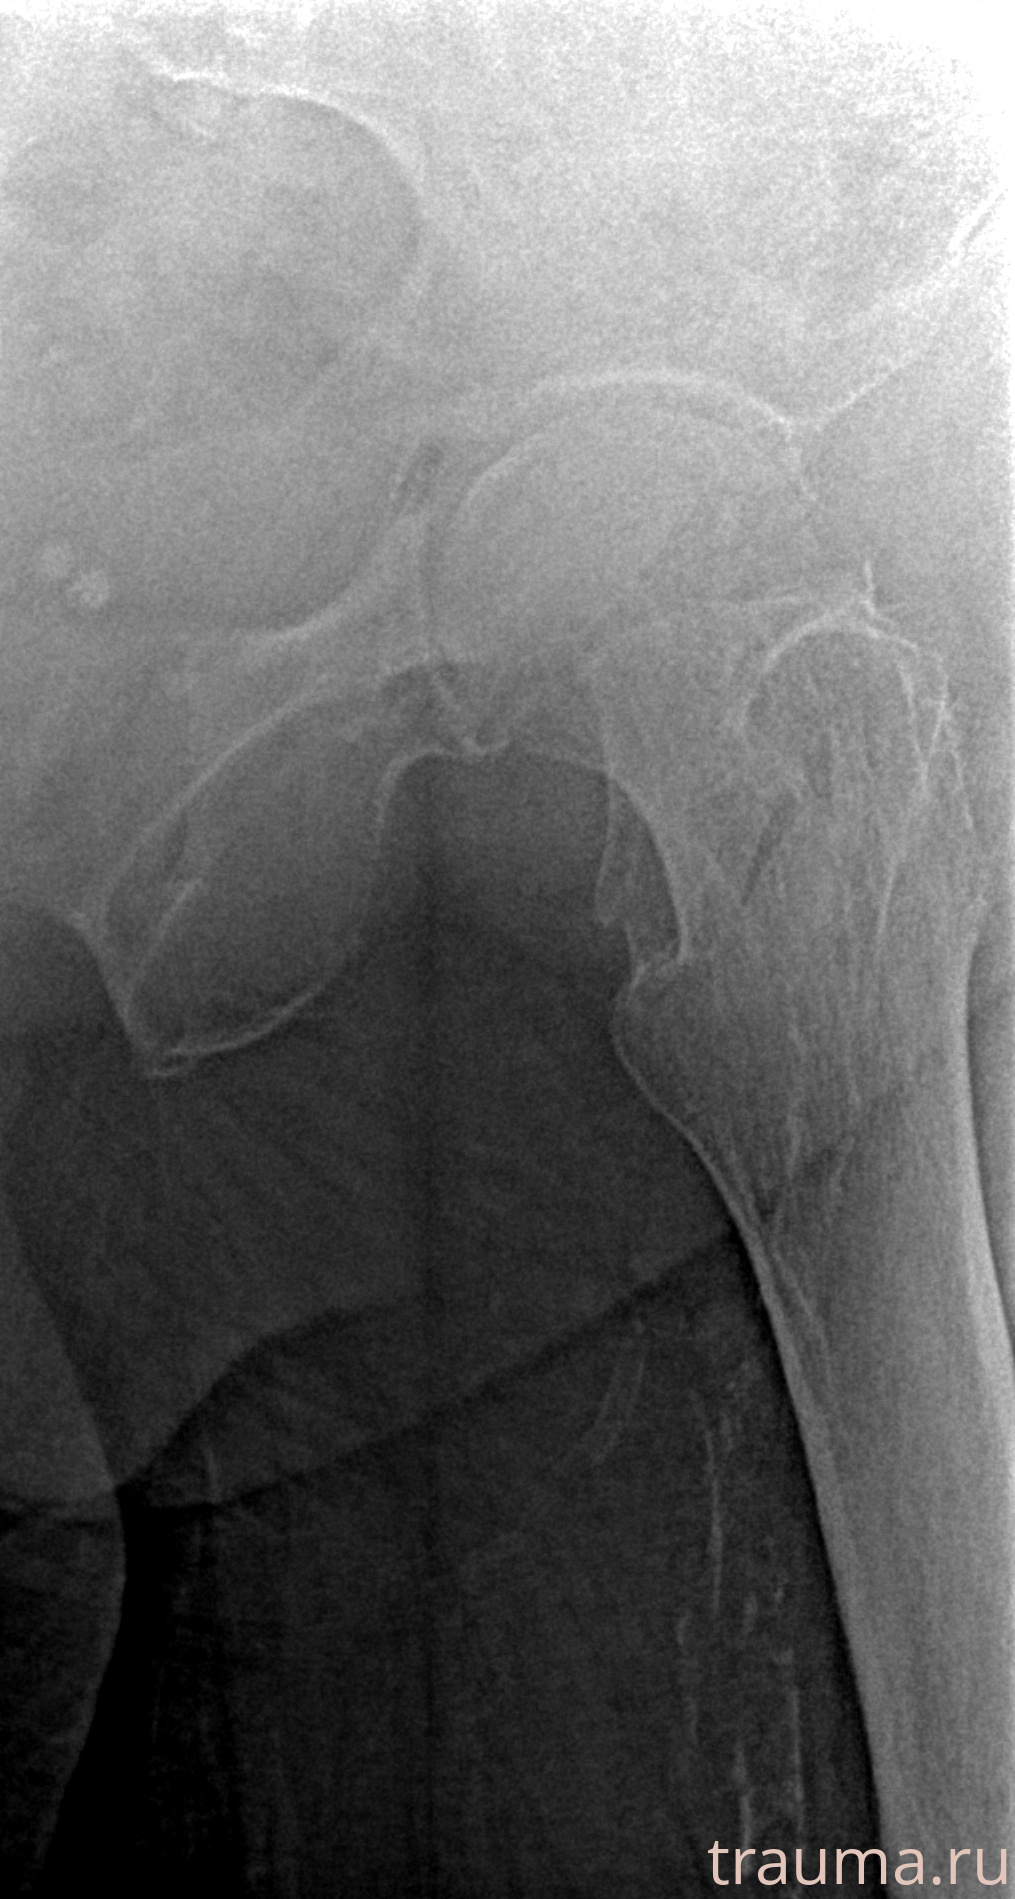

Рентген на дому: по вашему адресу приезжает врач-рентгенолог, травматолог-ортопед с мобильным рентгеновским аппаратом, проводит диагностику травмы или заболевания, делает необходимые рентгенограммы, дает рекомендации по дальнейшему лечению. Получить качественные снимки в домашних условиях возможно благодаря уникальной методике, разработанной МосРентген Центром для института  Склифосовского